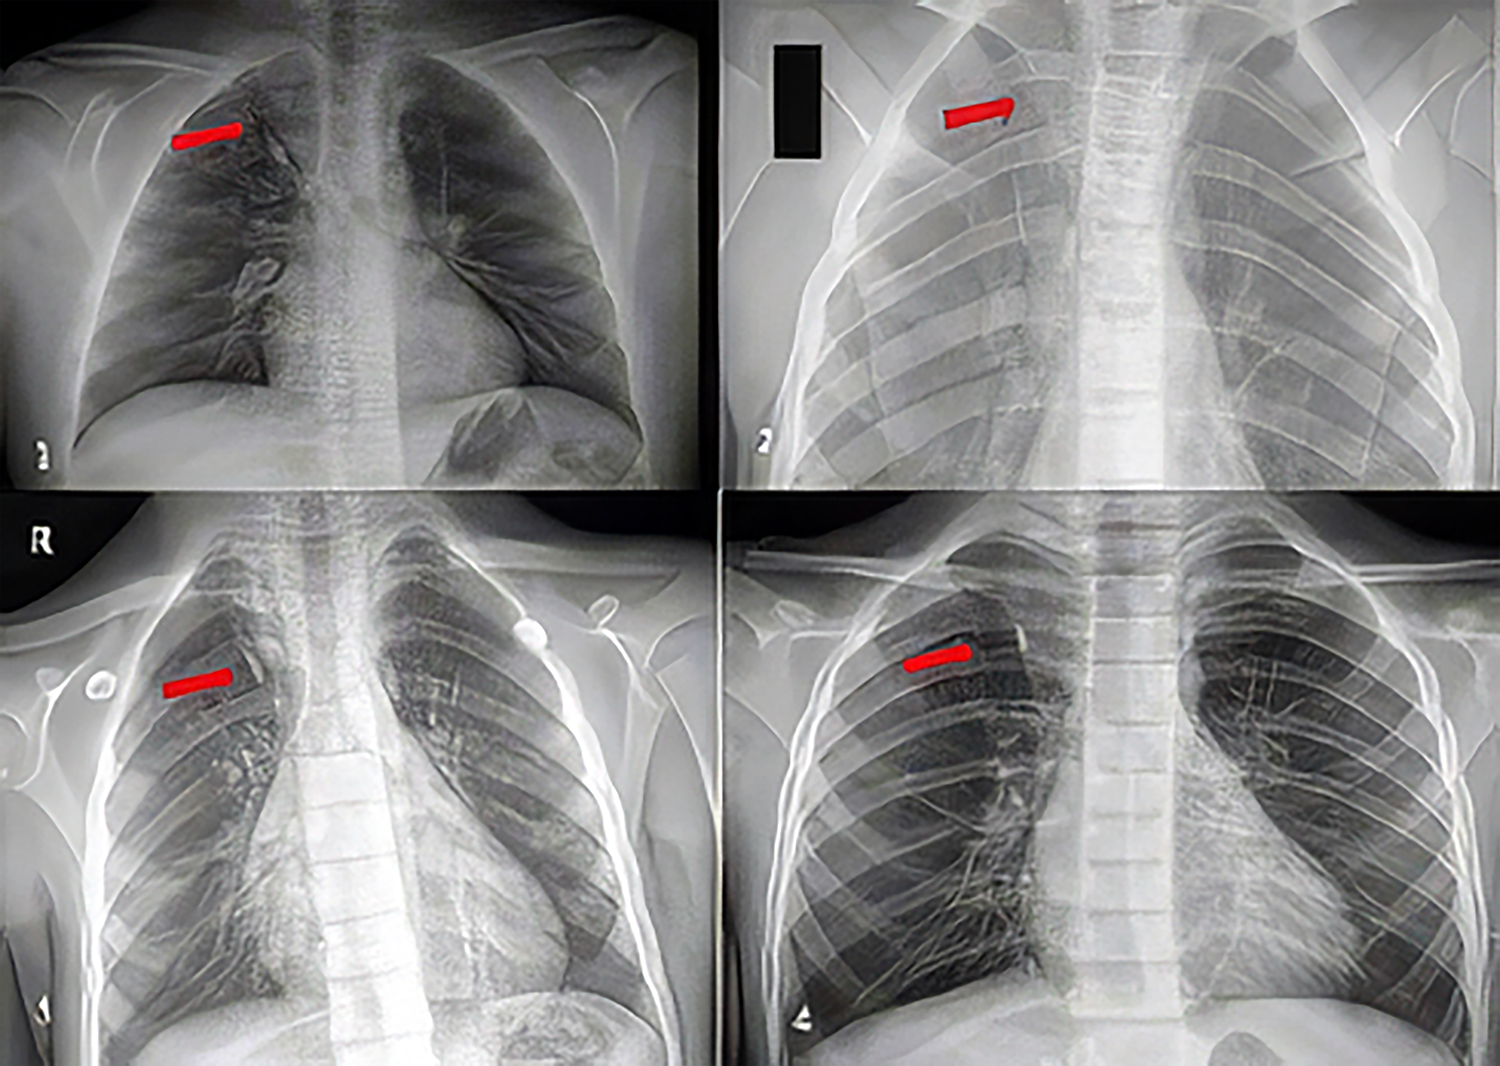

The demographic and clinical characteristics of the four patients with an azygos lobe are summarized in Table 1. Additionally, the postero-anterior chest X-rays are shown in Figure 1.

Figure 1. Chest X-rays of the patients (arrows indicate the azygos lobe)